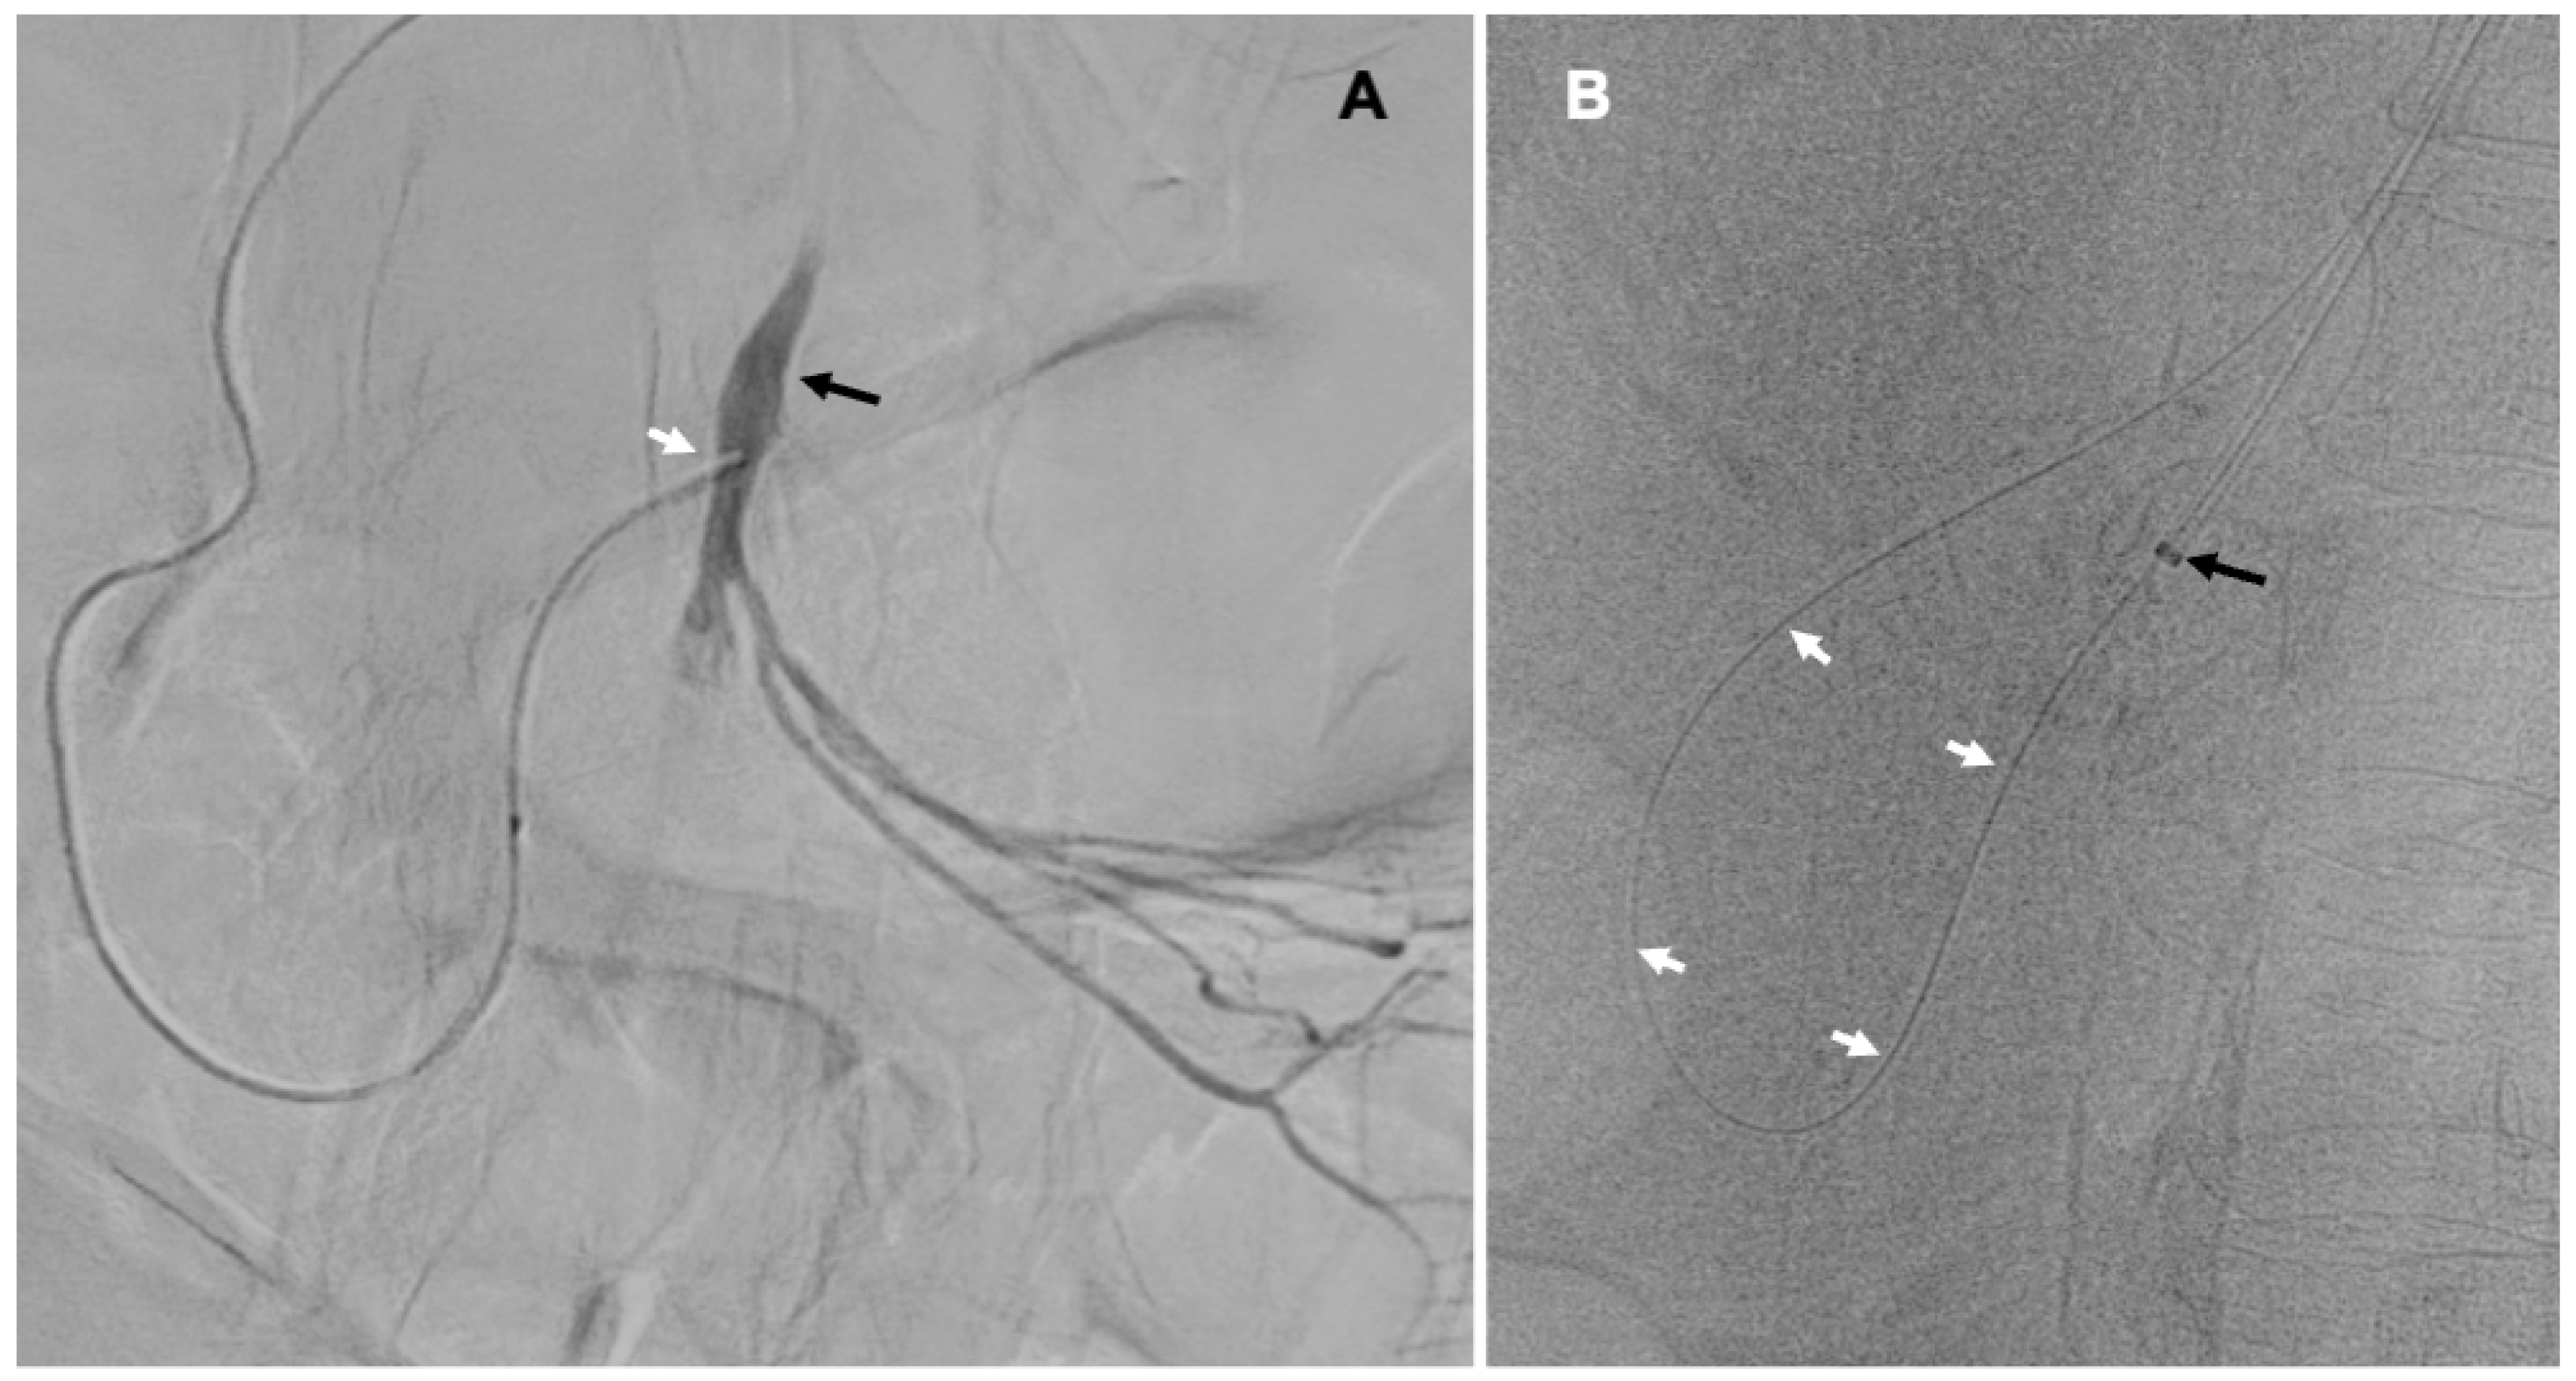

First, we introduced a 5F vertebral diagnostic catheter to the distal part of the CHA, then the coaxial Progreat microcatheter (Terumo, Tokyo, Japan), which was navigated through the GDA and the pancreaticoduodenal arteries (PDA) to the SMA distally from the occluding plaque (Figure 2A). Thereafter, the occlusion that was highly calcified was crossed with 0.014″ and then 0.018″ guidewires. From the right brachial access, we introduced another 6F introducer sheath, which was placed at the level of the SMA. Guidewire, which has been previously navigated to the abdominal aorta across the lesion through the celiac trunk, the CHA, the GDA, the PDA, and the proximal SMA, was caught with a loop (Figure 2B). Then, through the 6F introducer sheath, in an antegrade direction, we introduced 2.5/20 mm and 4.0/20 mm Trek coronary dilatation catheters (Abbott Vascular, Abbott Park, IL, USA), and with these balloons, we predilated the plaque under the pressure of 6–18 atm.

Figure 2.

(A)—Microcatheter (white arrow) advanced to the superior mesenteric artery (black arrow) through the gastroduodenal and pancreaticoduodenal arteries; (B)—Guidewire (white arrows) navigated in a retrograde manner across the lesion to the aorta caught to the introducer sheath (black arrow).